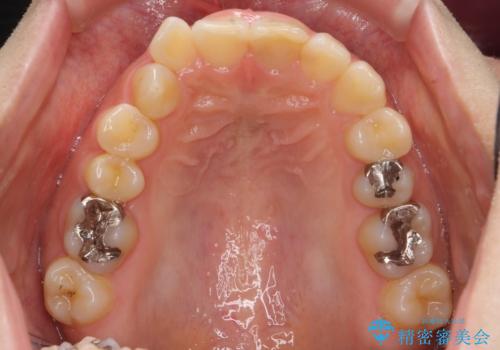

前歯のがたつき ガミースマイルの改善

- 前歯のがたつきとガミースマイルの改善を希望して来院。

ガミーは非常に軽度でひどくはなかったのですが、改善を強く希望されていました。

上の前歯をひっぱりあげて目立たなくするために、上の前歯のワイヤー部分矯正を行い、ミニスクリューからわずかに引っ張り上げました。

また、右上の犬歯の反対咬合についてもワイヤー矯正で短期間で改善することができました。

前歯の過蓋咬合についても改善しています。